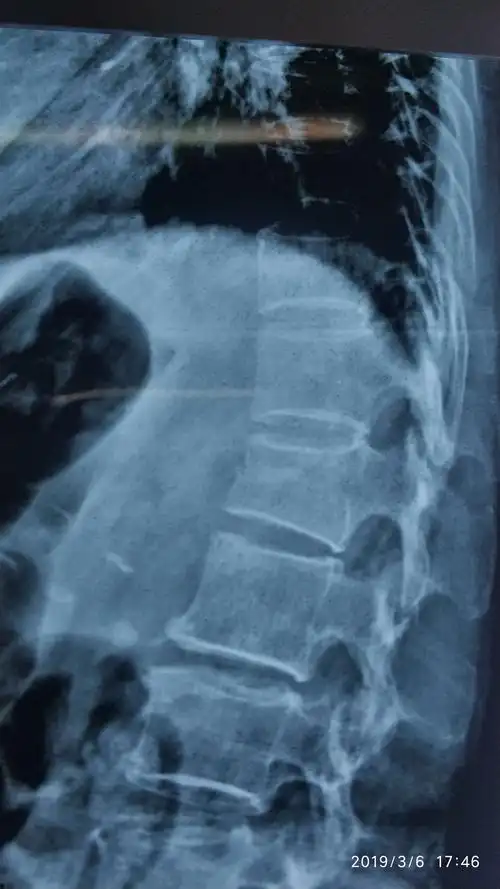

术前dr示腰1椎体压缩骨折

腰1椎体压缩性骨折经皮球囊椎体成形术

术前磁共振提示,腰1椎体压缩性骨折

腰椎平片提示腰1椎体前缘压缩有二分之一,侧位片非常明显,且腰椎ct

腰1椎体压缩骨折